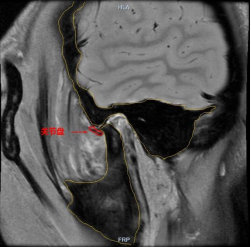

磁共振高清成像(≤2mm):对软组织分辨率高,可直观观察关节盘的位置、形态及运动情况,判断是否存在关节盘移位、穿孔或关节腔积液等。

(关节盘不可复性前移位的磁共振图片)